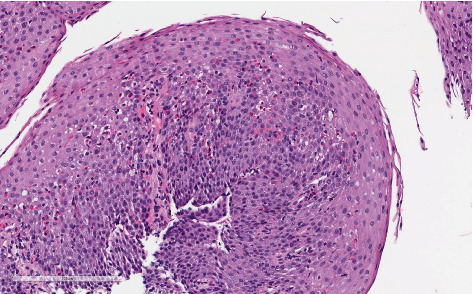

嗜酸性粒细胞性食管炎(EoE)是一种慢性免疫介导的疾病,以吞咽困难、食物嵌堵和食管嗜酸性粒细胞增多为特征,可导致纤维化和狭窄的形成。虽然纤维狭窄并发症在儿童中相对罕见,但研究表明,高达86%的成人EoE患者出现吞咽困难和食管狭窄,而儿童只有6%。此外,儿童狭窄形成的发生率仍然很低,报道的发生率约为3.4%。先前记录的患有这种并发症的最小的孩子是3岁。EoE患者纤维狭窄的危险因素包括年龄较大、病程延长和症状频率增加。这是已知的此类病例中最年轻的一例,表明纤维狭窄可能是该疾病的一种独特表型,而不仅仅是炎症形式的进展。考虑到早期狭窄发展的可能性,该病例强调了早期和彻底评估EoE的重要性。

Eosinophilic esophagitis (EoE) is a chronic, immune-mediated disorder characterized by dysphagia, food impactions, and esophageal eosinophilia, which can lead to fibrosis and the formation of strictures. While fibrostenotic complications are relatively rare in children, studies have shown that up to 86% of adults with EoE experience dysphagia and esophageal narrowing, compared to only 6% in children. Furthermore, the incidence of stricture formation in children remains low, with reported rates of approximately 3.4%. The youngest child previously documented with this complication was 3 years old. Risk factors for fibrostenosis in EoE include older age, prolonged disease duration, and increased symptom frequency. This represents the youngest known presentation of such a case and suggests that fibrostenosis may be a distinct phenotype of the disease, rather than merely a progression from the inflammatory form. This case underscores the importance of early and thorough evaluation of EoE, given the potential for early stricture development.